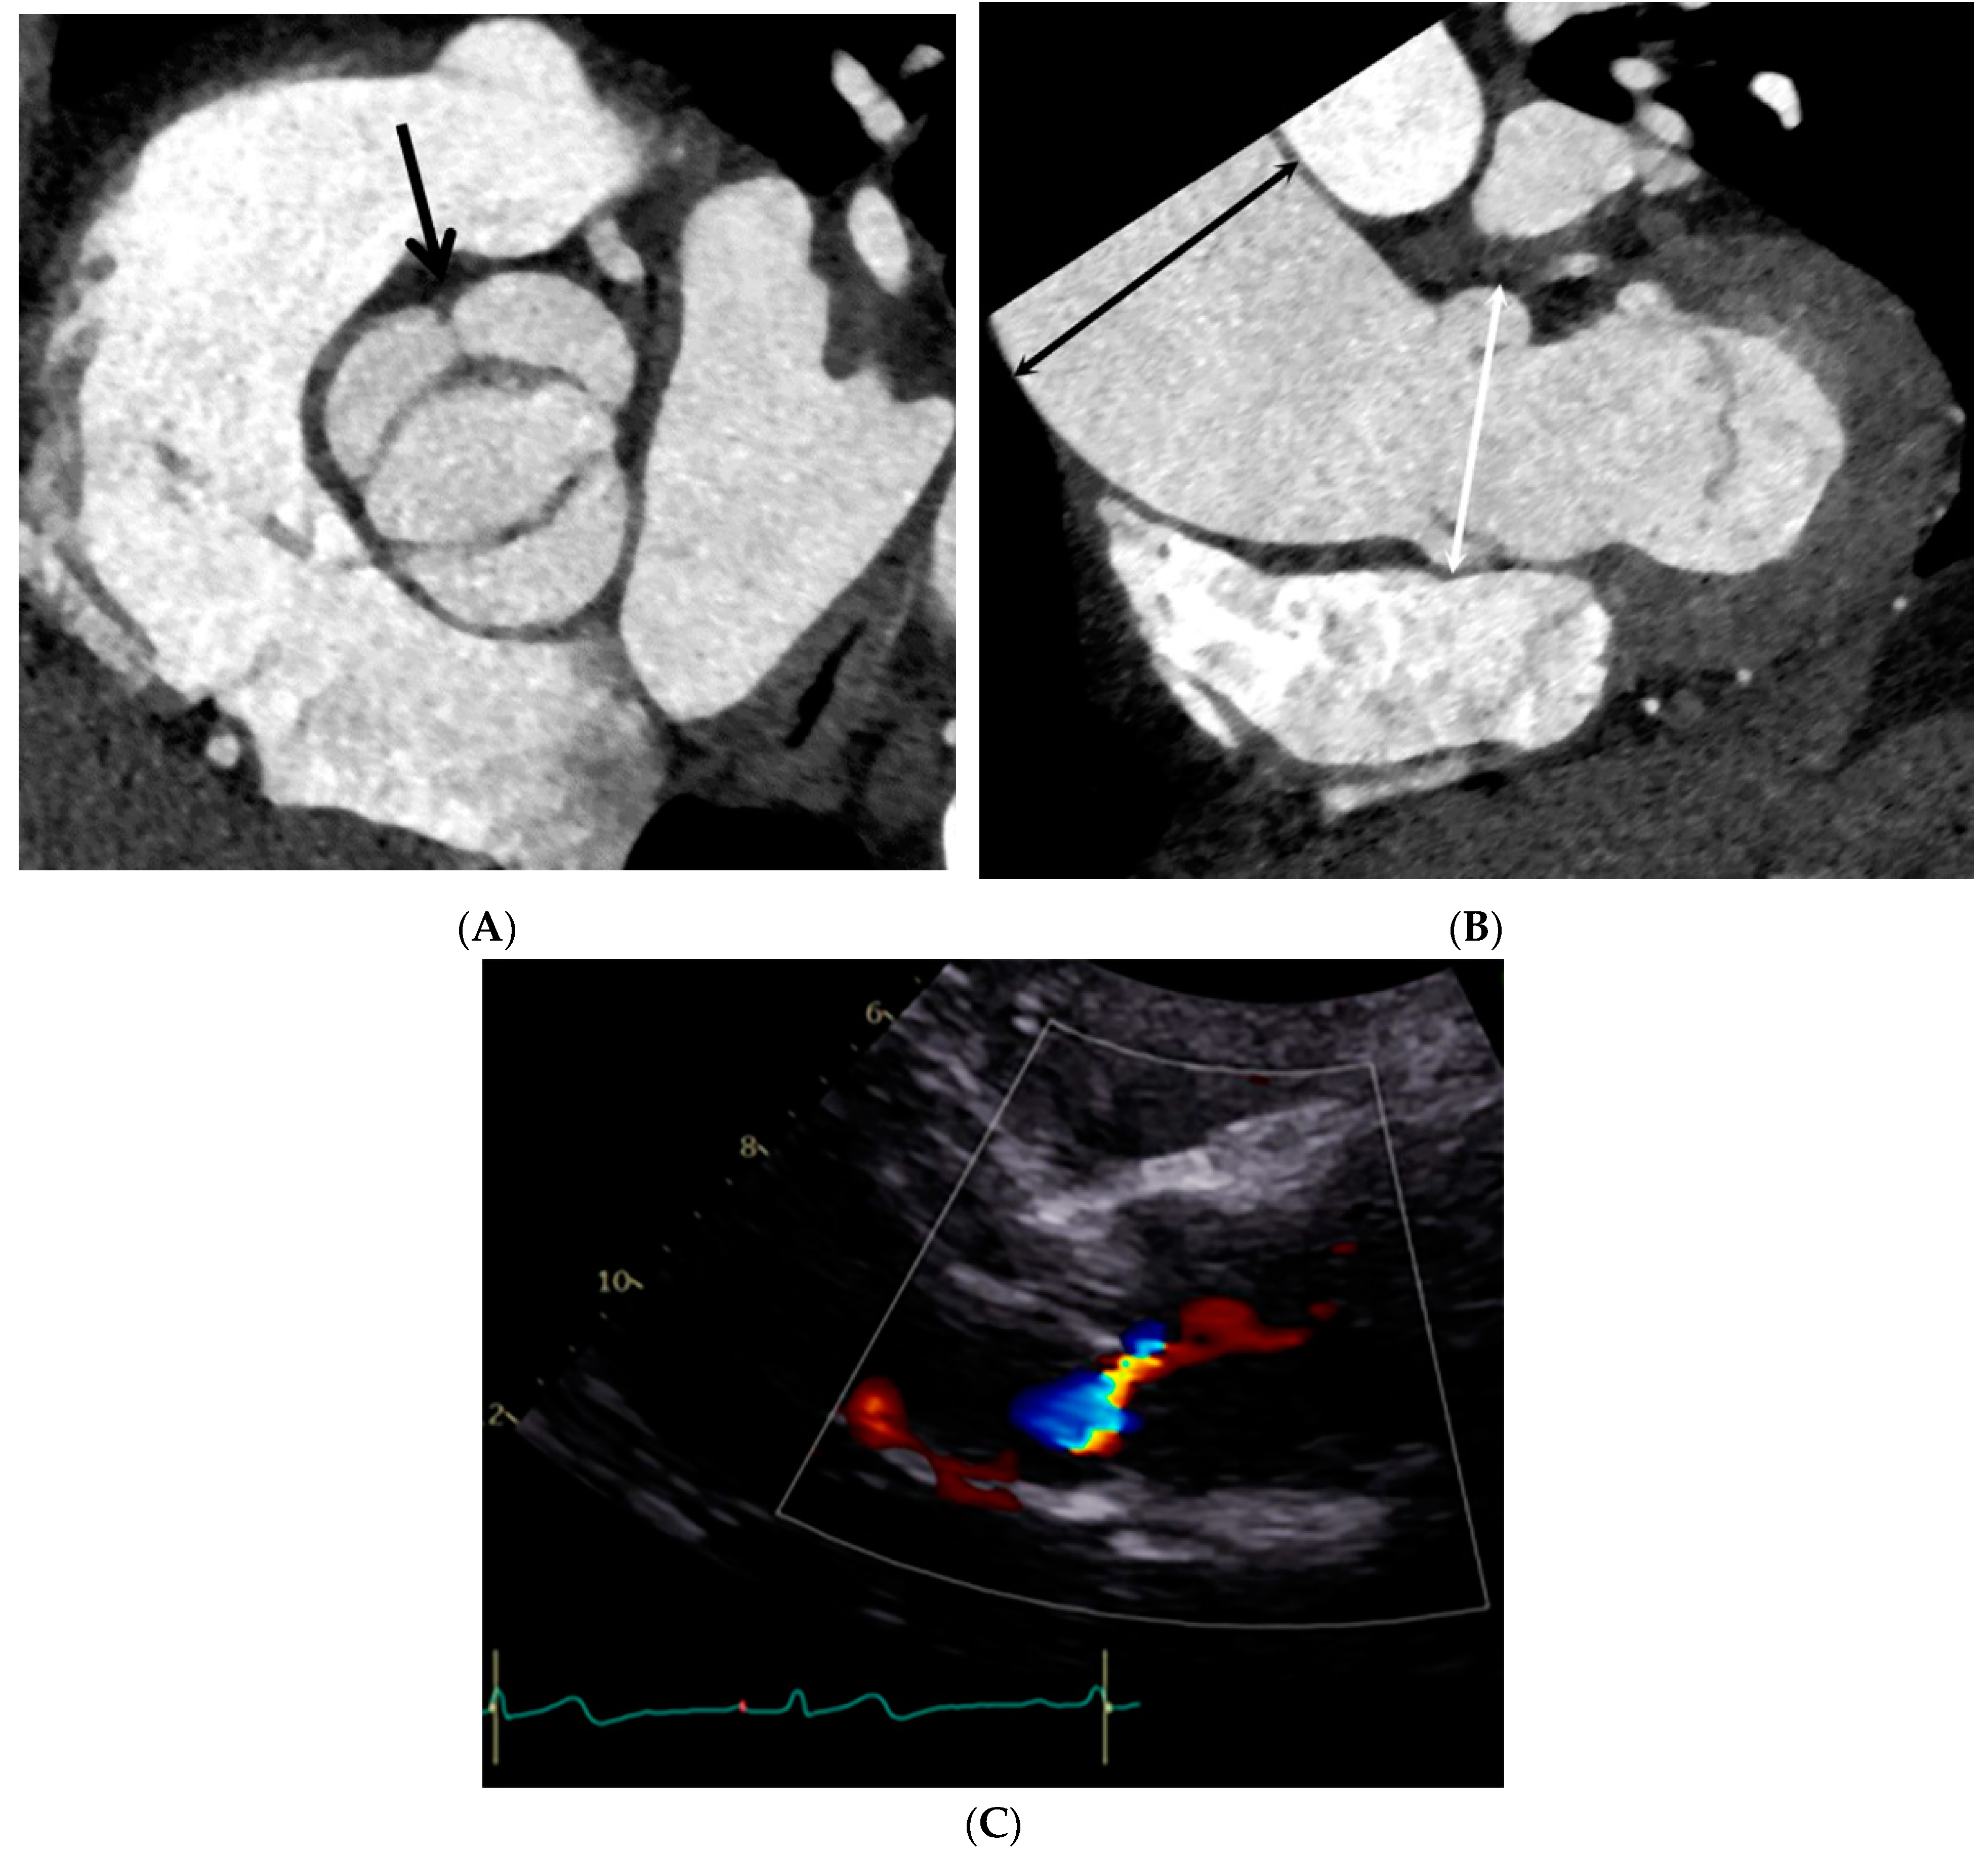

2.2. CT Imaging Protocols

2.3. CT Image Reconstruction and Analysis

2.4. Echocardiographic Evaluation